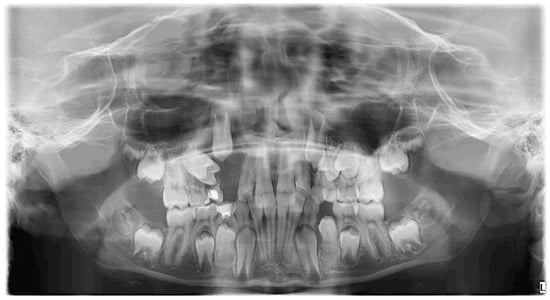

A preliminary investigation with a panoramic radiogram was ordered to disclose the presence of erupted and unerupted teeth with their possible developmental or positional abnormalities, as well as to assess the condition of surrounding maxillofacial structures. The radiolucent, unilocular area with a diameter of approximately 3 cm, extending in the area above Teeth 53 and 54, was observed (Figure 3).

Figure 3.

OPG before treatment.

That finding necessitated further diagnostics with CBCT (Figure 4, Figure 5, Figure 6 and Figure 7). A 3D radiograph confirmed a round, well-demarcated, noninflammatory cyst-like lesion extending from Teeth 11 to 15.